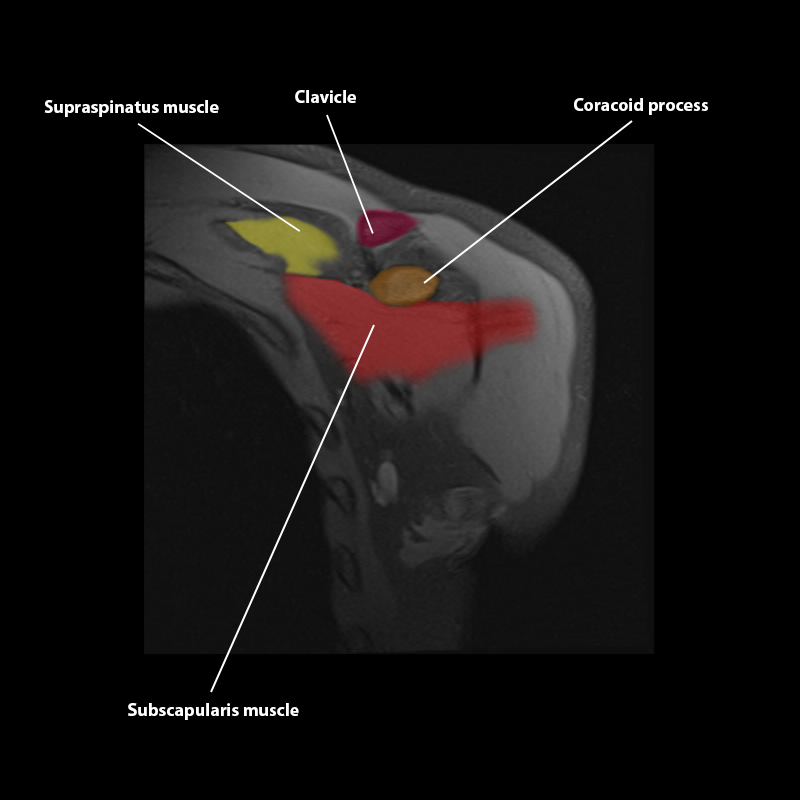

Shoulder MRI Anatomy